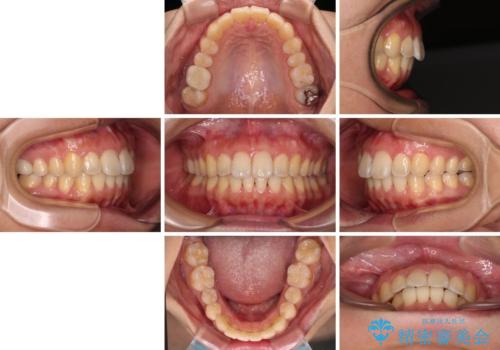

前に出ている前歯を引っ込めたい インビザライン矯正

- 前方に傾斜した上下の前歯を気にして来院された患者様です。

唇の閉じにくさや横顔のシルエットが気になるような突出感ではなかったため、インビザラインを用いて、歯列の遠心移動とIPR(歯と歯の間を削る)により前歯の傾斜を改善していくこととしました。

スムーズに終了すると思われましたが、インビザライン矯正独特の奥歯が咬み合わない状態が続き、更には遠方へ転居されたこともあり、治療期間は長引いてしまいました。